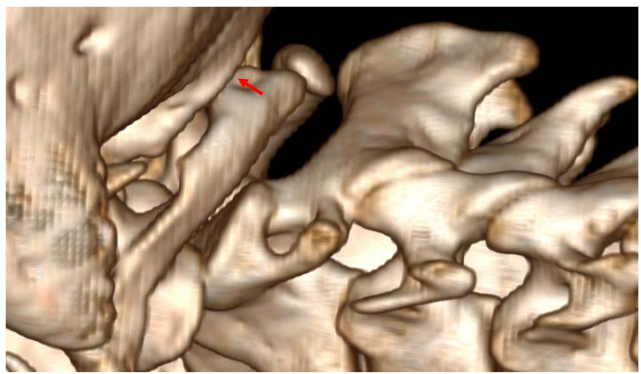

This case report describes a patient with chronic neck pain following cervical spine manipulation techniques. The patient presented with significant neurological symptoms on both sides of the neck, caused by combined end-range cervical rotation and extension. We decided not to proceed with axial MRI in these cases. We followed up with an axial view, which showed…

This study outlines a standardized protocol for magnetic resonance imaging (MRI) of the cervical spine using the 3T Siemens Skyra/Numaris4, Version Syngo MR E11. Utilizing a 20-channel Head and Neck coil, the imaging focuses on evaluating ligament integrity, particularly the atlas C1, through a combination of neutral and rotated positions.

Case Report Findings

We positioned the cervical spine in a rotated position, and the findings showed that the C1-2 segment placed under tension. The MRI results indicated a cross-sectional lesion to the Anterior Longitudinal Ligament illustrated in Figure 10.